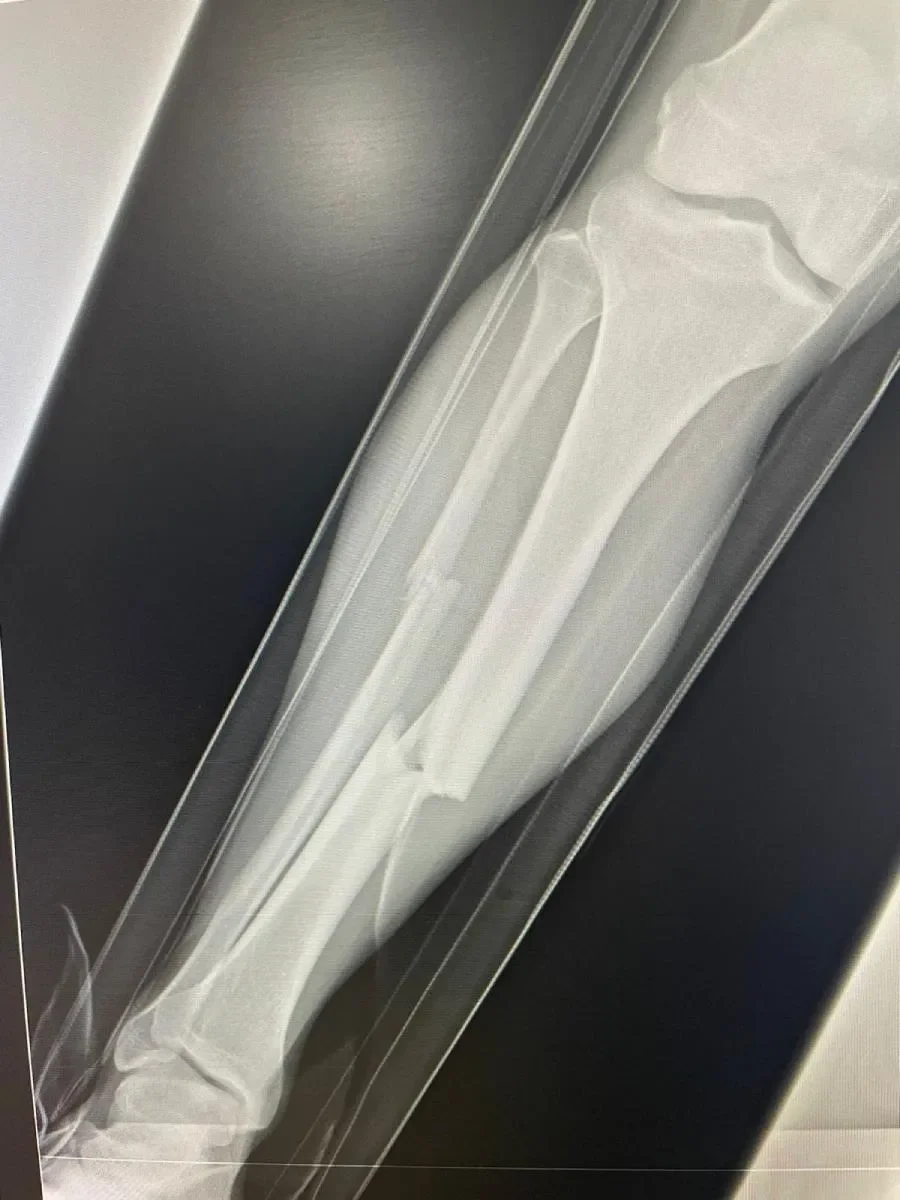

En cuanto Ruiz rompió a Bermúdez, el 'Hobbit' fue trasladado a un hospital de la Ciudad de México, en el que en cuanto llegó y se revisó que era fractura de tibia y peroné, los médicos le alienaron la pierna a Christian, para ayudar a la cirugía posterior.

Por la mañana del sábado, Bermúdez ya fue operado y en cuanto recuperó conciencia, le aseguró a la directiva azulgrana, encabezada por Emilio Escalante y Jorge Santillana: “Voy a regresar”. El médico que lo atendió, Jesús Felipe González, comentó a los cercanos del Hobbit que le sorprendió la mentalidad positiva con la que encara el proceso.